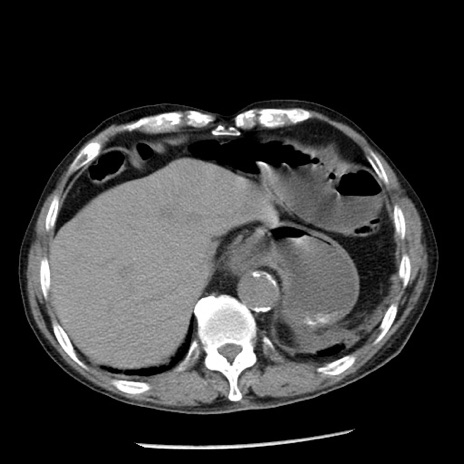

症例26(横断像)

【症例】80歳代男性

【主訴】嘔吐

【現病歴】昨晩2回嘔吐あり、今朝になっても嘔吐あり。来院。

【既往歴】胃潰瘍

【身体所見】意識清明、BT 37.6℃、BP 166/95mmHg、HR 100bpm、SpO2 97%、腹部:平坦・軟、腸蠕動音聴取良好、圧痛なし。

【データ】WBC 21900、CRP 1.46